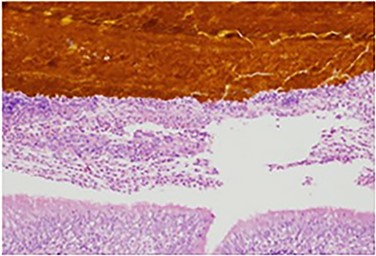

Laparoscopic cholecystectomies represent one of the most common procedures of General Surgery. Dropped gallstones during laparoscopic cholecystectomy is a rare occurrence but can potentially lead to morbid complications. We present a rare case of a broncho-pleuro-cutaneous fistula in a patient with recurrent abscess formations after an elective laparoscopic cholecystectomy. The fistula formed over 3 years from a gallstone that eroded through the diaphragm, into the pleural space, and eventually into a terminal bronchiole. Bilirubin staining within the fistula tract was confirmed on hematoxylin and eosin staining.

The patient recovered well, but <1 month later he noticed an additional draining sinus at the right flank. A fistulogram (Fig. 1) was performed, and it showed a connection between the sinus and a right lower lobe bronchiole. He was taken to the OR for a right thoracotomy with wedge resection of the right lower lobe of the lung and excision of a broncho-pleuro-cutaneous fistula that was found to contain pieces of golden pigmented solid material, which was concluded to be consistent with a gallstone (Fig. 2). This case report presents a patient with an uncommon complication from a dropped gallstone: a broncho-pleuro-cutaneous fistula.

Specimen histology demonstrating bilirubin deposits within the lung parenchyma